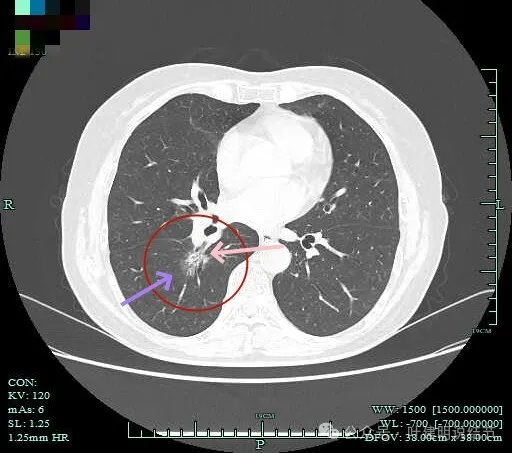

病灶出现,淡磨玻璃密度,但轮廓较清,且表面不平。

病灶内部有走行的支气管,但显得有些僵硬;病灶表面有浅分叶。

灶内血管走行,轮廓与边界清楚。